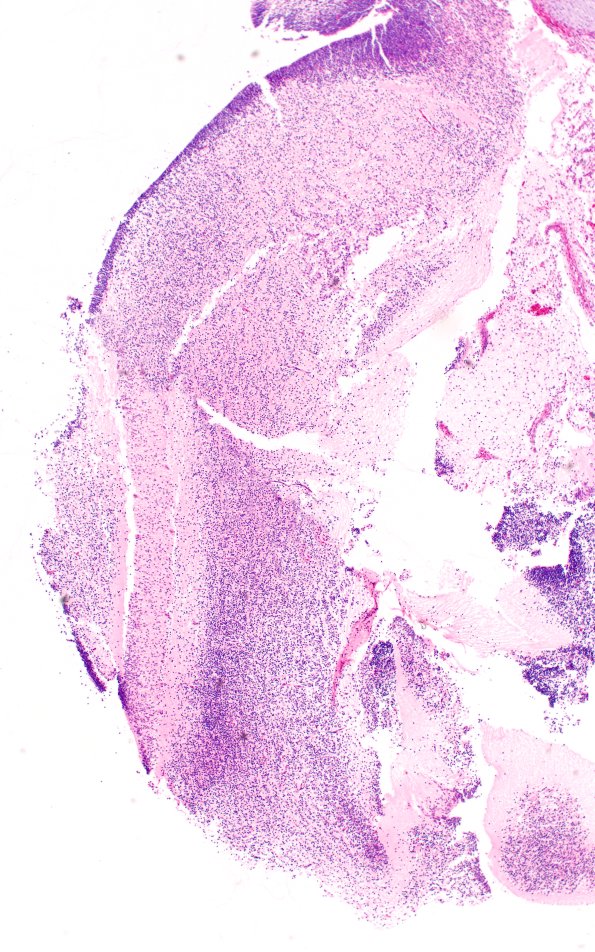

Washington University Experience | DEVELOPMENTAL MALFORMATIONS | Encephalocele | 1B3 Myelomeningocele (Case 1) H&E 4X 2

A closeup of the encephalocele contents. There are patches of embryonal elements which are largely intact. (H&E)